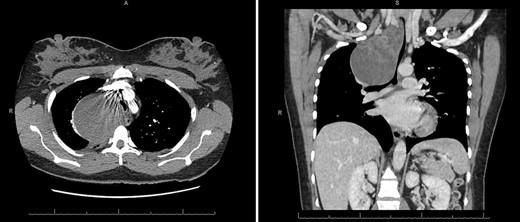

The patient ultimately presented again in March 2020, with symptoms including chest and neck pain, dysphagia and dyspnea at rest that began a few days prior to presentation. On physical exam, the patient was tachypneic and tender to palpation on the right side of her neck, chest and back. CT angiogram demonstrated an 8 cm × 10 cm × 7.4 cm non-enhancing, low-attenuation mass in the right middle mediastinum extending to the right superior mediastinum, abutting the medial aspect of the right lung apex causing significant external compression of the distal trachea (Fig. 1).

CT axial and coronal views demonstrating the right middle mediastinal mass (8 cm × 10 cm × 7.4 cm) with distal tracheal extrinsic compression.